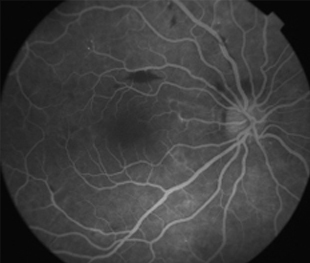

2 meses: disminución de manchas algodonosas y hemorragias con mejoría de circulación

Funcional

OD - 0,50 esf 0,9 +2

OI -0,25 esf 1,00